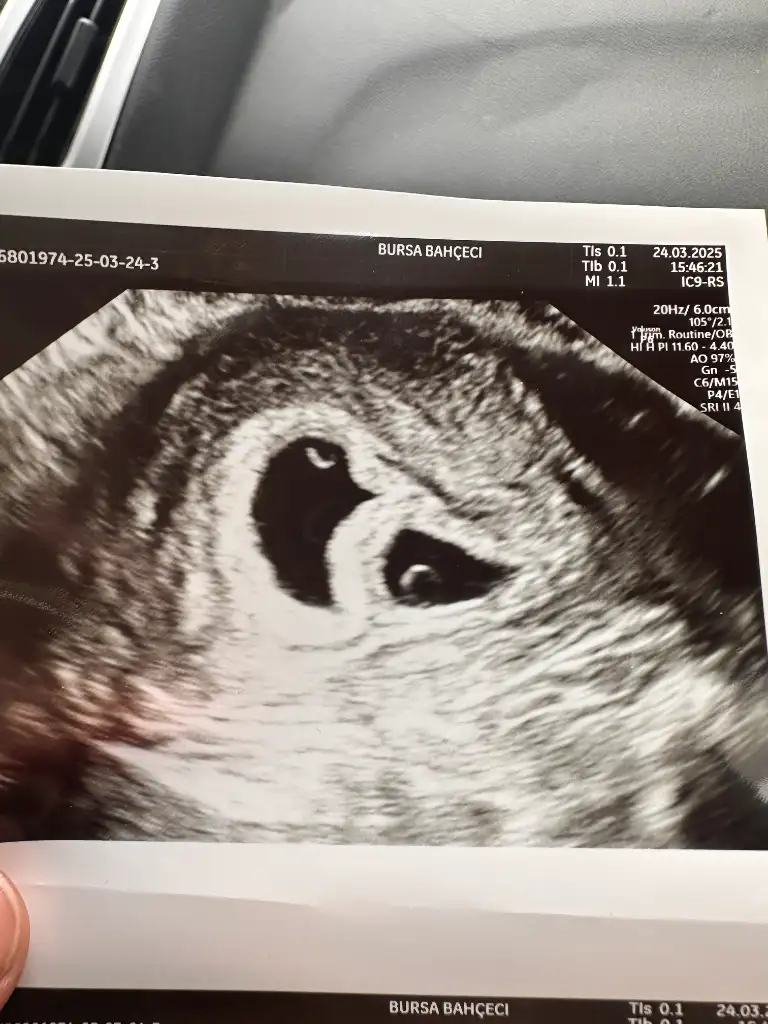

Canım benimki bariz belliydi doktor direk ikiz ikiside tutmuş dedi

Ultrason fotoğrafı verdim sanaCanım benimki bariz belliydi doktor direk ikiz ikiside tutmuş dedi

Tabi canım bir maşallahınızı alırım kızlarUltrason fotoğrafı verdim sana

Yani belli olmaz ikiz de olabilirOyyy maşallah maşallahhh

Senin ikiz olabilir birisi arkadan geliyor ama önemli değil önemli olan sağlıcakla büyümesi sonradan kardeşini yakalar inşallahAllah razı olsun doktorum bile bana bu kadar bilgi vermiyor![]()

İnanın ultrasyon boş hiç birşey yok şaşırdım bende bilen birine attım keseyi zor gördüSenin ikiz olabilir birisi arkadan geliyor ama önemli değil önemli olan sağlıcakla büyümesi sonradan kardeşini yakalar inşallahultrason resmini tam atsaydın belki

Şöyle varmı kiSenin ikiz olabilir birisi arkadan geliyor ama önemli değil önemli olan sağlıcakla büyümesi sonradan kardeşini yakalar inşallahultrason resmini tam atsaydın belki

Ya bir ben görmüyorumEvet iki kese gördüm![]()